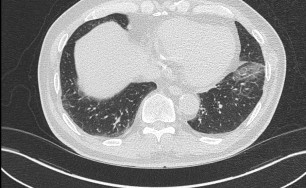

숨케어한의원에서는 전화예약을 받고 있습니다. 내원시 엑스레이, CT사진, 폐기능검사지를 가지고 오시면 자세한 상담이 가능합니다.